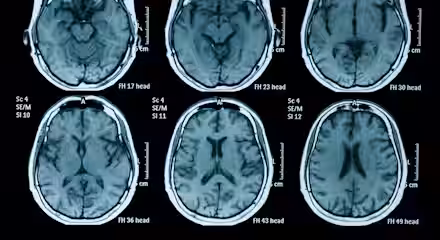

In stroke care, every minute counts. Around two million brain cells are lost for each minute a stroke goes untreated. Rapid intervention can mean the difference between a full recovery and a lifetime of disability, or even death.